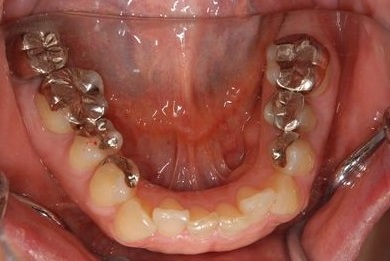

治療前

• 治療前